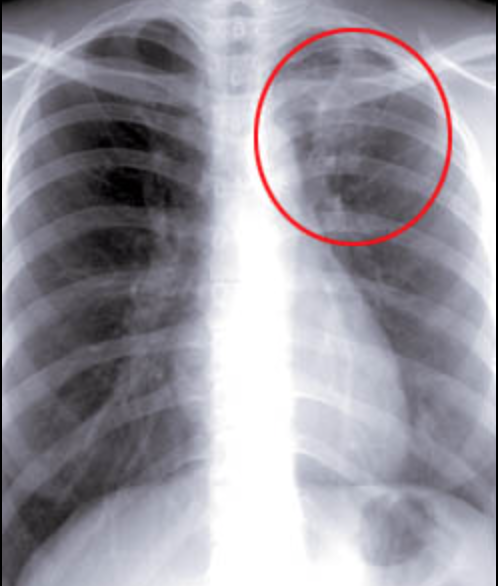

결핵이 의심된다면 흉부 엑스레이, 객담검사, 필요시 CT 검사까지 받을 수 있으며, 대부분 국가에서 검사비를 지원합니다.

결핵은 대표적으로 폐에 생기는 감염병인 폐결핵 형태로 흔하게 발생합니다.

증상은 흔한 감기 증상과 비슷하지만, 지속 기간과 동반되는 이상 증상들을 보면 차이를 알 수 있습니다.